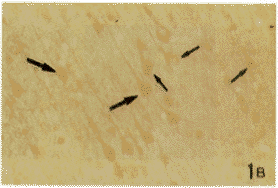

图1A 大鼠大脑皮质mGluR1和ER双重免疫组织化学染色切片。短箭头(↑)所指与B图中相应部位的↑所指为同一细胞。长箭头(↑)所指为mGluR1/ER双标细胞,并与B图中相应部位的↑所指为同一细胞。小三角(▲)所指为mGluR1阳性(单标)细胞,大三角(▲)所指为ER阳性(单标)细胞。图1B为A的相邻连续切片。IL-2免疫组织化学染色。短箭头(↑)所指与A图中相应部位的↑所指为同一细胞。长箭头(↑)所指为IL-2阳性细胞,并与A图中相应部位的↑所指为同一(三标)细胞 ×100

Fig.1 A mGluR1 and ER double immunostained section of the cerebral cortex.Short arrow(↑)points the same cell in corresponding position of B and pointed by ↑.Long arrow(↑) points mGluR1/ER double labeled cell,which is the same cell in corresponding position of B and pointed by ↑.Small triangle(▲) points mGluR1-positive(single labeled)cell.Large triangle(▲)points ER-positive(single labeled)cell.B:IL-2 immunostained serial neighbor section of A.Short arrow(↑) points the same cell in corresponding position of A and pointed by ↑.Long arrow(↑) points IL-2 labeled cell.which is the same cell in corresponding position of A and pointed by ↑ (triple-labeled cell). ×100

在大鼠大脑皮质、延髓和脊髓颈、胸、腰段均可见到mGluR1,ER和IL-2免疫反应性神经细胞。mGluR1免疫反应产物为蓝黑色,位于胞膜;ER免疫反应产物为棕褐色,位于胞浆或核内。IL-2免疫反应产物亦为棕褐色,位于胞浆内。在大脑皮质,上述3种阳性细胞分布于皮质各层,以第Ⅴ层最为密集。在数量上,mGluR1阳性细胞最多,ER阳性细胞次之,IL-2阳性细胞最少。阳性细胞以锥体形大、中细胞为主(图1A,B)。在延髓和脊髓,mGluR1和ER阳性神经元的分布已述于我们的另一篇文章[8],主要分布于迷走神经背核、孤束核、三叉神经脊束核和网状结构及脊髓的腹角、背角和中间带,以mGluR1阳性神经细胞占优势,以上细胞以中等大多角形细胞为主(图2A,3A,4A)。IL-2阳性细胞在延髓和脊髓的分布均较上述两种细胞少(图2B,3B,4B),但分布类型相似。本实验主要对大脑皮质、延髓网状结构和脊髓腹角的含上述免疫、神经、内分泌3类物质的细胞进行研究。在mGluR1和ER双重染色的切片上,可见3种细胞:(1)mGluR1单标细胞,胞膜为蓝黑色;(2)ER单标细胞,胞浆或胞核呈棕褐色;(3)mGluR1/ER双标细胞,胞膜为蓝黑色,胞浆和胞核为棕褐色。双标细胞约占全部(单+双)标记细胞的50%~60%(依部位而异,图1A,2A,3A,4A)。双标细胞的形态主要为锥体和多极细胞。通过对相邻两张切片的投影核对,证实在大鼠大脑皮质、延髓网状结构和脊髓腹角内存在mGluR1/ER/IL-2三重标记细胞,即同一神经细胞既为mGluR1/ER阳性,又呈IL-2阳性,1个细胞在相邻两张切片上的影像重迭(比较图1A与1B,图2A与2B,图3A与3B,图4A与4B)。三标细胞约占mGluR1/ER双标细胞总数的30%。